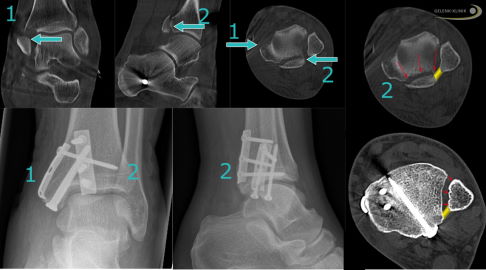

Wie behandelt man fehlverheilte knöcherne Ausrisse der Syndesmose?

Die Bandplastik ist bei direkter Schädigung der Bandstruktur sinnvoll. Kam es im Rahmen der Verletzung zu einem Ausriss der Syndesmose, kann es auch im Verlauf noch sinnvoll sein, diese Knochenverletzung wieder aufzulösen und zu rekonstruieren. Die Bandanteile sind hierbei ja am Knochen noch befestigt.

Fehlverheilte Verletzungen nach knöchernen Syndesmosenausrissen gibt es in verschiedenen Ausprägungen und an verschiedenen Stellen. Der Ansatzbereich der Syndesmose kann besonders bei frischer Verletzung gut direkt versorgt werden. Ein vorderer oder hinterer knöcherner Ausriss muss bei entsprechender Größe direkt später mit Repositionierung therapiert werden. Unser primäres Ziel ist es, diese Verletzungen für eine gute Prognose möglichst gut wiederherzustellen.

Bei nicht optimaler Wiederherstellung der Knochenstellung (Reposition) nach knöchernem Ausriss der Syndesmose ergeben sich fast unvermeidbar Folgeschäden. Meist resultiert eine bleibende massive Syndesmoseninstabilität. Ob eine Operation angeraten ist, hängt immer auch von der Größe der Bandfragmente ab und wie genau der Ausriss verläuft.

Insbesondere bei Erstdiagnostik und Erstbehandlung werden abhängig vom Verletzungsmuster unterschiedliche Behandlungsansätze und operative Behandlungen durchgeführt. Aktuelle Studien konnten nachweisen, dass eine möglichst optimale Ausrichtung der Sprunggelenksgabel wesentlich zur Stabilität im Schienbein-Wadenbeingelenk beiträgt.

Bei unzureichender Positionierung des Wadenbeins in der Sprunggelenksgabel kann sich im Röntgenbefund unter Belastung und im DVT eine sogenannte Diastase darstellen - ein nach außen hin vergrößerter Abstand der beiden Unterschenkelknochen.